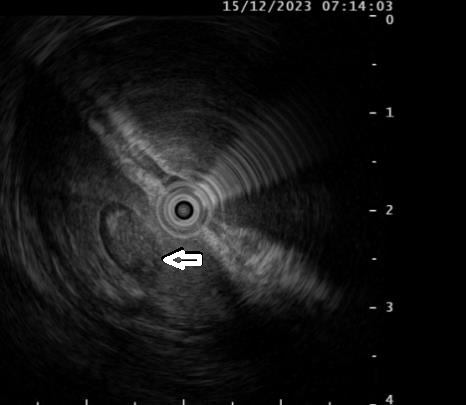

超声内镜:胃壁第2、3层内见一椭圆形混合回声

5天前,王女士误服枣核,之后出现上腹部隐痛,进行性加重,并伴有发热、恶心等症状,自服多种胃药治疗,症状未改善。来院就诊行胃镜检查提示:胃窦大弯侧见一约1.5cmX1.0cm的广基隆起,表面粘膜光滑。进一步行超声内镜扫查显示:胃壁第2、3层内见一椭圆形混合回声区域,边界清晰,切面大小约1.0cmX0.5cm,结合病史,确诊为胃脓肿。